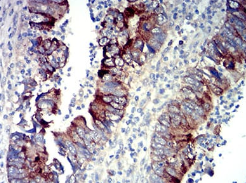

P2RY14 Mouse Monoclonal antibody[8A11B]

IHC    1/200 - 1/1000